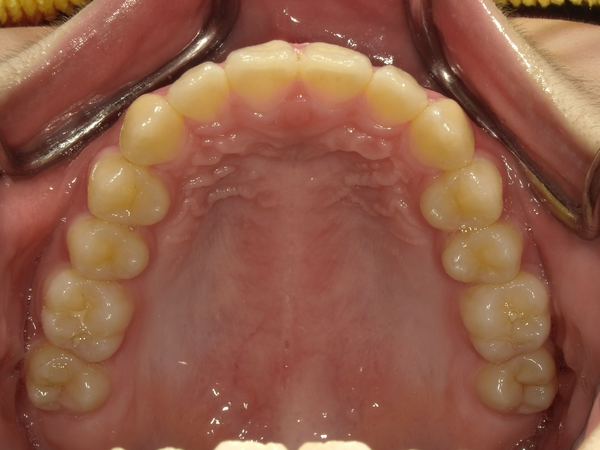

すきっぱ(空隙歯列)CASE5 2023.06.19 10代女性非抜歯〇ご相談内容:上前歯のすきっぱ〇矯正の種類:マウスピース型矯正「インビザラインGO」〇治療期間:14週間〇治療費用:44万円(税込) < すきっぱ(空隙歯列)CASE6すきっぱ(空隙歯列)CASE4 > ブログ記事一覧をみる